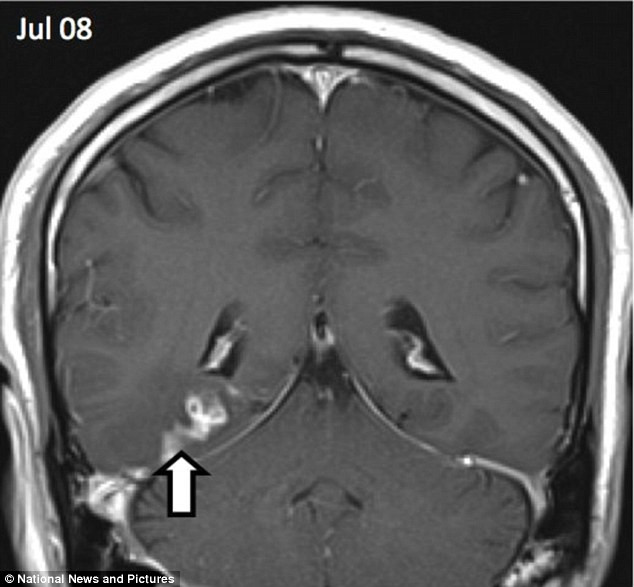

Đây là loạt các hình ảnh quét não cho thấy con đường sán dây siêu nhỏ kí sinh ở não một người đàn ông ở Anh trong 4 năm.

Kết quả chụp X-quang cho thấy: một con sán dài 1cm làm tổ ở bán cầu não phải đang di chuyển sang phía bán cầu não trái.